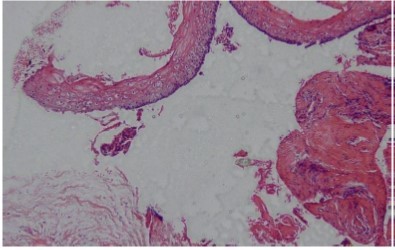

According to the microscopic analysis of the incisional biopsy of the anterior mandibular lesion extending from the mesial left canine to the right first premolar, epithelial detachment from the connective tissues was observed in some areas of the cystic structure lined with para-keratinized stratified squamous epithelium. The connective tissue of the cyst wall was fibrocollagenous with diffuse infiltrates and the inflammatory cells were mainly chronic and comprised islands of odontogenic epithelium with a marginal band of cylindrical cells resembling ameloblasts. Blood vessels, nerves, muscles, extravascular hemorrhage and hemosiderin pigment were observed. The microscopic observations confirmed the diagnosis of inflammatory odontogenic keratocysts (Figure 5 and Figure 6). The patient underwent marsupialization in the symphysis and the lateral ramus for treatment and was then followed up with for the purpose of this study for 8 months.No recurrence was seen.

Figure 5.Hematxylin-eosin staining, Para-keratinized stratified squamous epithelium covering the inflammatory odontogenic keratocysts (×10)